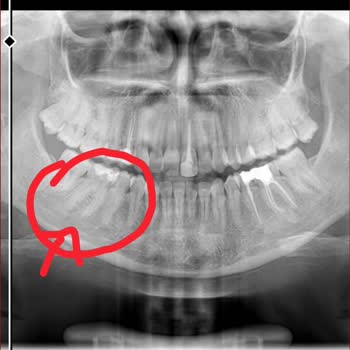

Adana Seyhan’daki Fatma Kemal Timuçin Diş Hastanesi’nde, doktor **** tarafından yapılan implant tedavim sırasında ve sonrasında hem sağlık açısından hem de davranış açısından çok olumsuz bir süreç yaşadım. İmplantlarımdan rahatsız olduğumu, sorun yaşadığımı doktora ilettiğimde, kendisi bana hakaret ...